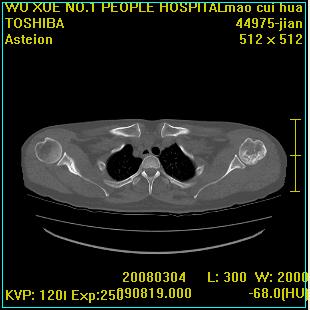

标题: CT12025:男,50岁,左肩活动受限半年。 [打印本页]

标题: CT12025:男,50岁,左肩活动受限半年。

肩关节骨质破坏呈小囊状,其周软组织轻度肿胀,余未见异常。

考虑:肩袖损伤。建议mri。

左侧肱骨头密度不均匀,高低混杂,周围软组织略肿胀,考虑结核性病变。

左侧肱骨头密度不均匀,高低混杂,髓腔密度稍高,周围软组织略肿胀,肌间隙模糊,考虑慢性骨髓炎可能。密切结合临床!